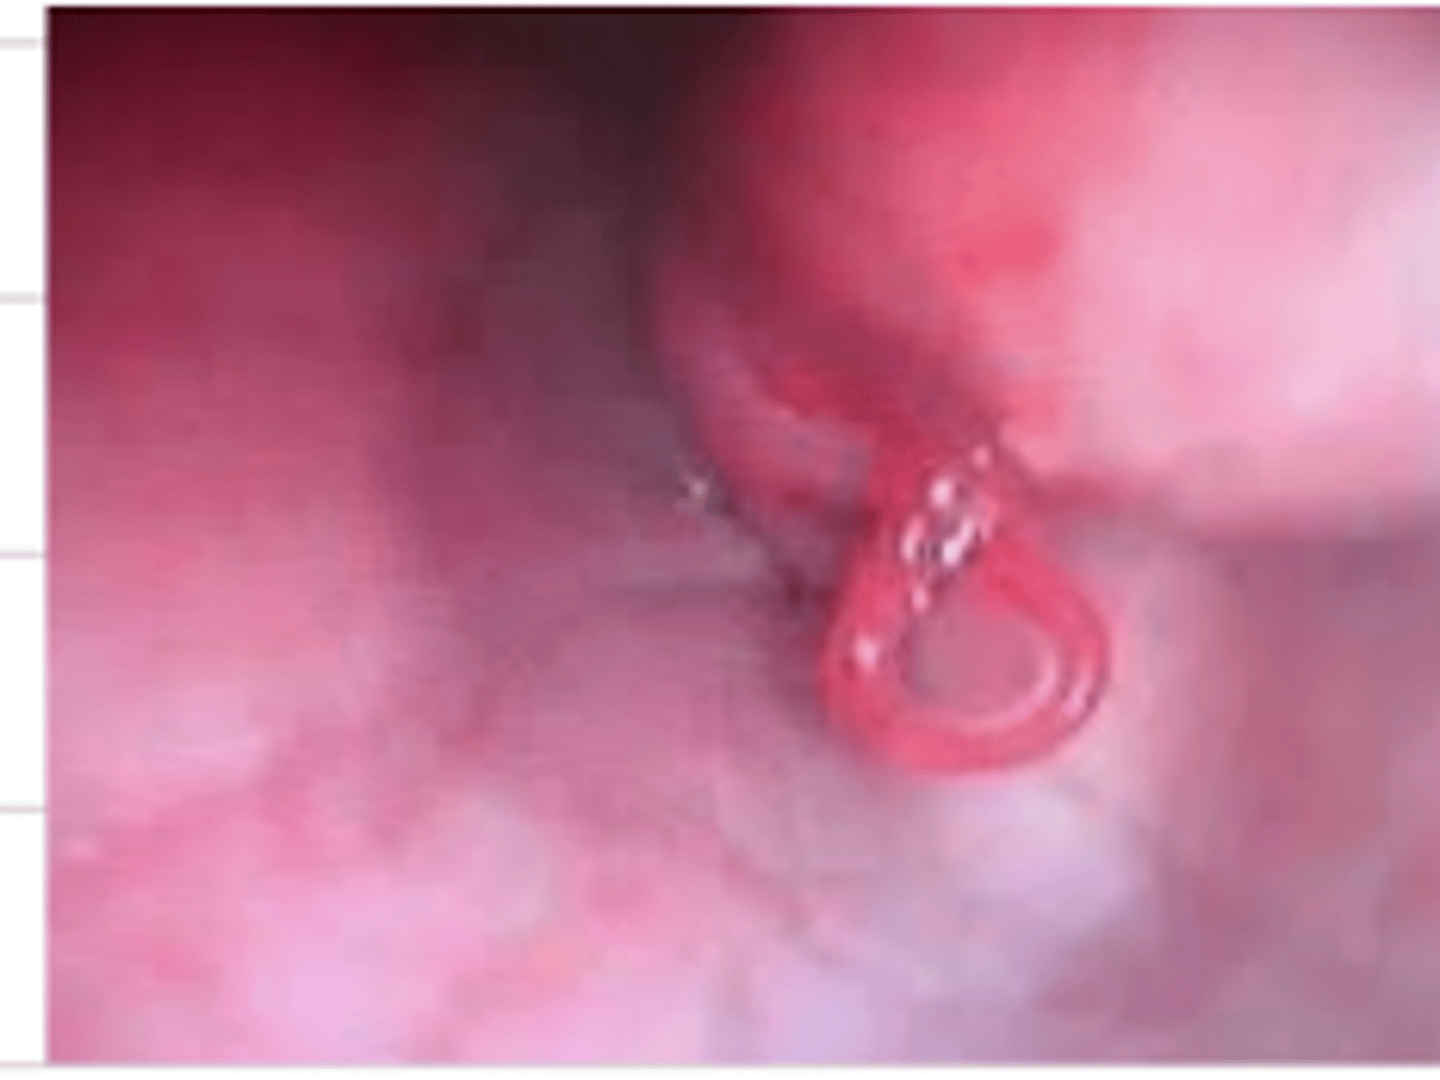

parasite in the esophagus (Spirocerca lupi)

what is the problem we see here?

Spirocerca lupi

what is the most common parasite we will find in the esophagus of a dog?